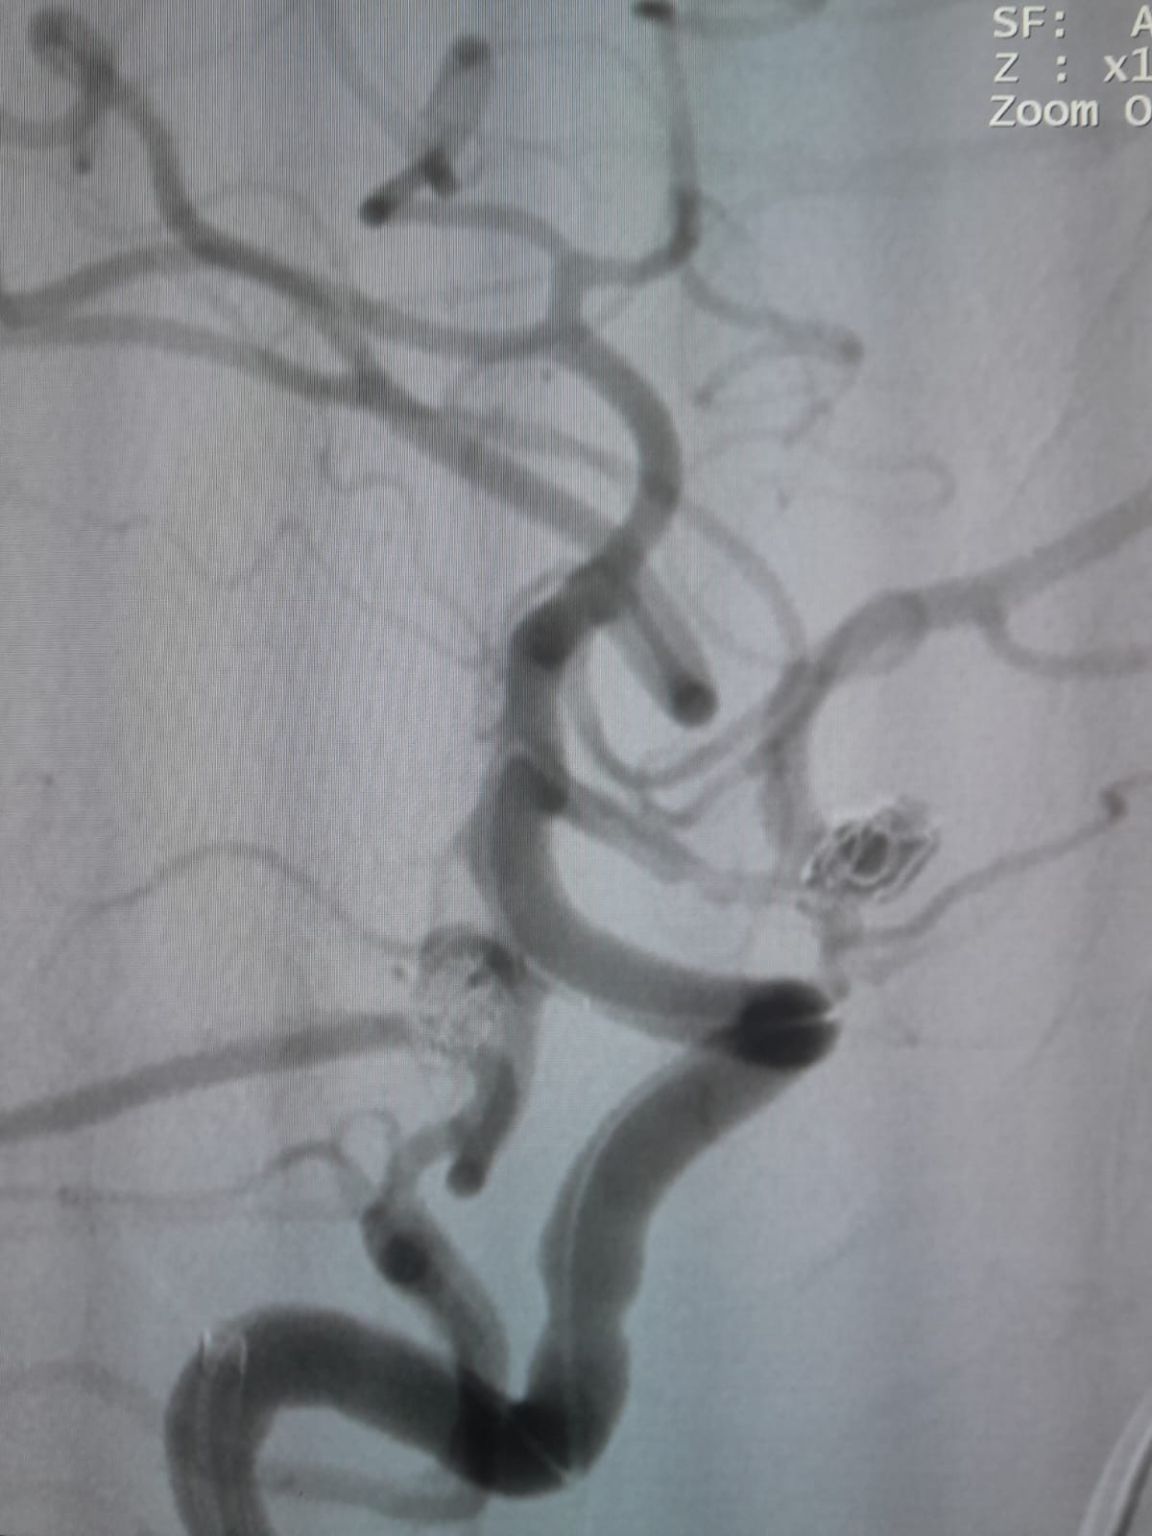

Le patient a été diagnostiqué avec un anévrisme sacculaire de l'artère communicante antérieure (AComA) nouvellement découvert et un anévrisme de l'artère communicante postérieure (PComA) qui avait été précédemment traité avec l'embolisation de la bobine. L'imagerie de suivi a révélé un remplissage résiduel dans l'anévrisme PComA, nécessitant une intervention supplémentaire.

Anévrisme de l'artère communicante antérieure

L'accès vasculaire a été établi et l'équipe a ensuite navigué avec succès le Frepass®Microcathéter jetable (TJMC14) au site cible. L'embolisation a été réalisée à l'aide de trois Perdenser®Système Embolic Coil (TJCST4.508-3D, TJCST0306-3D, TJCST0206-3D) déployé avec le Deromper®Contrôleur de détachement de bobine (TJCDC).